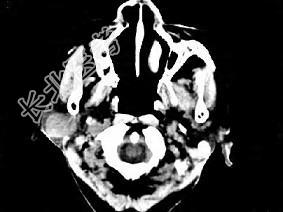

- 单项选择题女,72岁, 六年前于右面颊部扪及一包块,缓慢增大, 其表面较光滑,CT如图所示, 该病例应诊断为 ( )

A、Worthin瘤

B、腮腺混合瘤

C、颈部神经纤维瘤

D、颈部淋巴瘤

E、小唾液腺瘤